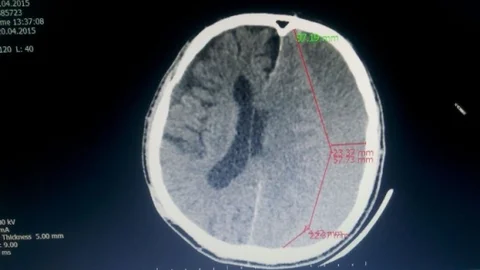

Anamur | 416 1…415416417…1037416/1037 Hamamönü Sanat Galerisi'nde Tel Kırma Sergisi Açıldı Pazarlar'da Voleybol Turnuvası Başladı Farklı Dillerle Bayram Coşkusu Recep Hacıeyüpoğlu'ndan Esnaf Açıklaması Serdivan'da 54. Cadde Projesi Açıklandı Sapanca'da 23 Nisan Mesajı Yayınlandı Muğla'da MHP Adayları Açıklandı Sapanca'da Regaip Kandili Mesajı Sakarya'da Hastalara Ağız Sağlığı Eğitimi Verildi Sapanca'da Duygusal Evlilik Teklifi Sakarya Meydan Muharebesi'ne Özel Müze Projesi Ebra Cömert'ten Talimatlar Geldi Canik'te Temsili Başkan Devir Teslimi Emet'te İnşaat Kazası Oluştu Cappy'den Yeni Ürün Tanıtımı Kulp'ta Sanatla Buluşma Anı Eskişehir'de Acı Bir Kaybımız Var Prof. Dr. Süleyman Uludağ'dan Tasavvuf Üzerine Konferans Gazi Emet İlköğretim Okulu Başarı Elde Etti Kocaeli'de Kamyonet Kazası Demirci'de Kore Gazisi Uğurlandı Altındağ'da Öğrencilere Destek Ziyareti Senegal'de Jandarma Eğitimi Verildi Pursaklar'da 50 Kadın Sertifika Aldı Kalp Hastasına Lokal Anestezi ile Ameliyat Yapıldı Pasinler'de Çocuklar Başkan Oldu Kulp'ta Başkanlık Devir Teslimi Yapıldı 1…415416417…1037416/1037 Anamur Haber Merkezi • 03 Kasım 2025 04:17 Facebook X WhatsApp Google News'te Abone Ol 03 Kasım 2025 04:17